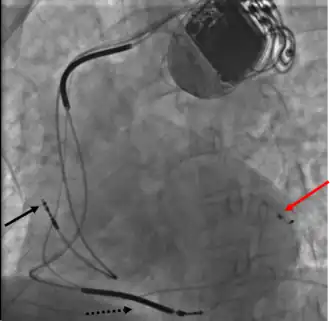

Dispositivo implantado para terapia de ressincroniação cardíaca

A terapia de ressincronização cardíaca (ing. Cardiac Resynchronization Therapy, CRT) - é um tratamento da ,  insuficiência cardíaca congestiva, que envolve o implante de eletrodos no coração para "cardioestimular" de forma sincrônica ambos ventrículos. Em alguns casos, também é possível estimular apenas o ventrículo esquerdo.